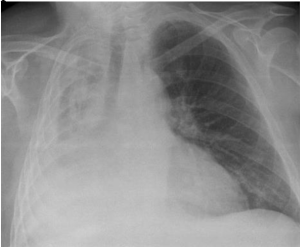

Tn. Kurapika, berusia 59 tahun datang ke RS dengan keluhan batuk sejak 2 bulan terakhir. Keluhan disertai sesak yang tidak berkurang dengan istirahat. Pada pemeriksaan tanda- tanda vital didapatkan TD 130/80 mmHg, HR 80x/mnt dan RR 26x/mnt dan suhu 37C. Pada pemeriksaan didapatkan perkusi pekak pada seluruh lapangan hemithoraks kanan. Pada pemeriksaan radiologi didapatkan sebagai berikut. Apakah kemungkinan diagnosis pasien tersebut?